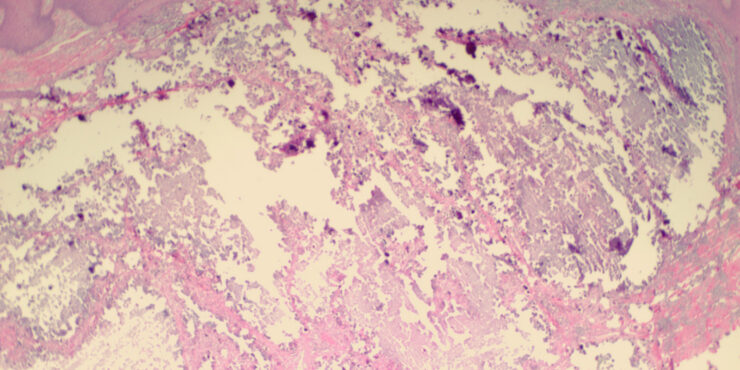

Read MoreCalcinosis Cutis = الكلاس الجلدي OLYMPUS DIGITAL CAMERA OLYMPUS DIGITAL CAMERA Calcinosis Cutis There are four forms of calcinosis cutis: metastatic calcinosis cutis, dystrophic calcinosis cutis, idiopathic calcinosis cutis, and subepidermal calcified nodule. Metastatic Calcinosis Cutis Metastatic calcification develops as the result of hypercalcemia or hyperphosphatemia. Hypercalcemia may result from (a) primary hyperparathyroidism, (b) […]